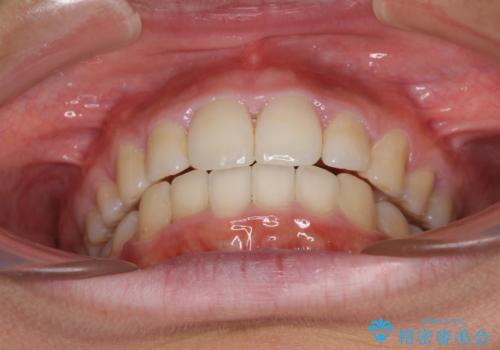

途中で来院されない時期があったため、期間が長引き、更には磨き残しが多かったことで虫歯が多く発現してしまいました。

しっかりと通院するようになってからは順調に治療が進み、横顔の印象が変わるほどスッキリとした口元となりました。